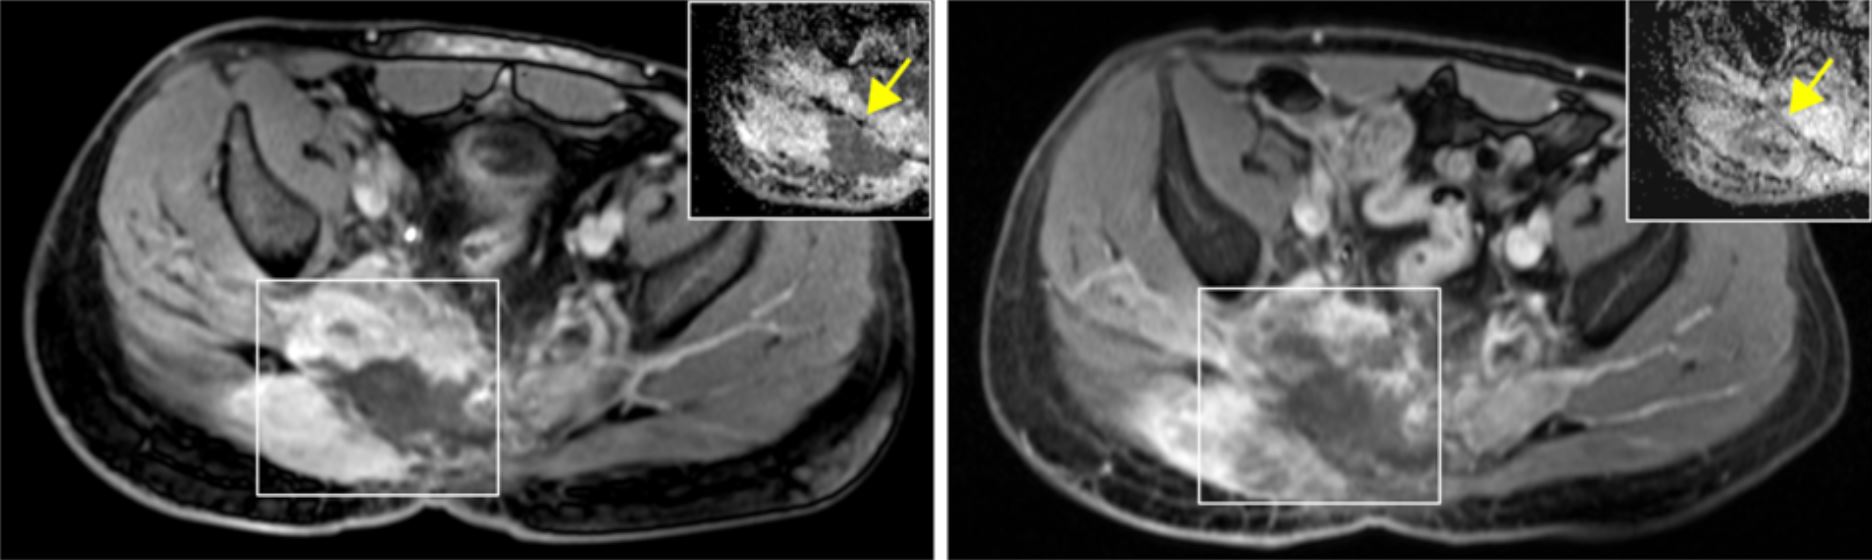

BU: links: Patient mit fortgeschrittenem Chordom; rechts: Stillstand des Tumorwachstums nach fünf Monaten Behandlung mit PARP-Inhibitor

Da sich bei anderen Krebsarten, bei denen ebenfalls ein HR-Defizit vorliegt, bestimmte Arzneistoffe als wirksame Medikamente erwiesen haben, lag es nahe, diese auch bei Chordom-Patienten als weitere Behandlungsoption einzusetzen. Die Ärzte führten bei einem Betroffenen mit passendem genetischem Profil eine experimentelle Behandlung mit einem so genannten PARP-Inhibitor durch. PARP-Inhibitoren hemmen das Enzym Poly-ADP-Ribose-Polymerase (PARP) und verhindern dadurch, dass Krebszellen Schäden an ihrer DNA, die etwa in Folge einer Chemotherapie auftreten, wieder reparieren können. Bei dem behandelten Patienten führte die Gabe eines PARP-Inhibitors zu einer langanhaltenden klinischen Verbesserung und einem Stillstand des Tumorwachstums. Nach erneutem Fortschreiten der Erkrankung bei demselben Patienten konnte das Team um Stefan Fröhling, Stefan Gröschel und Robert Russell vom BioQuant Heidelberg eine neuartige Resistenzmutation des PARP1-Enzyms identifizieren, welche die Wirkung des PARP-Inhibitors aufhob.